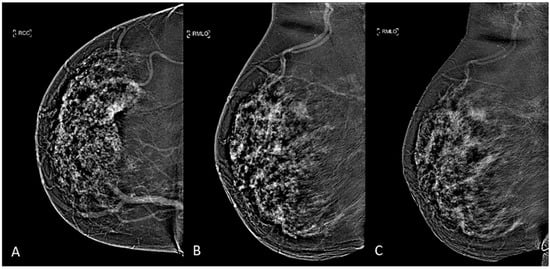

The two previously acquired images are then digitally subtracted of each other to produce a resultant recombined image that highlights contrast enhancement uptake area and gives functional information [10], as it can be seen in Figure 1. Four and eight minutes after contrast agent administration, each breast were compressed in the MLO view: early-MLO and late-MLO view images were respectively acquired (Figure 1).

Figure 1.

CEM subtracted images of a multifocal IDC in a 53-years-old woman with dense breast: (A) CC view, (B) early-MLO view, (C) late-MLO view.